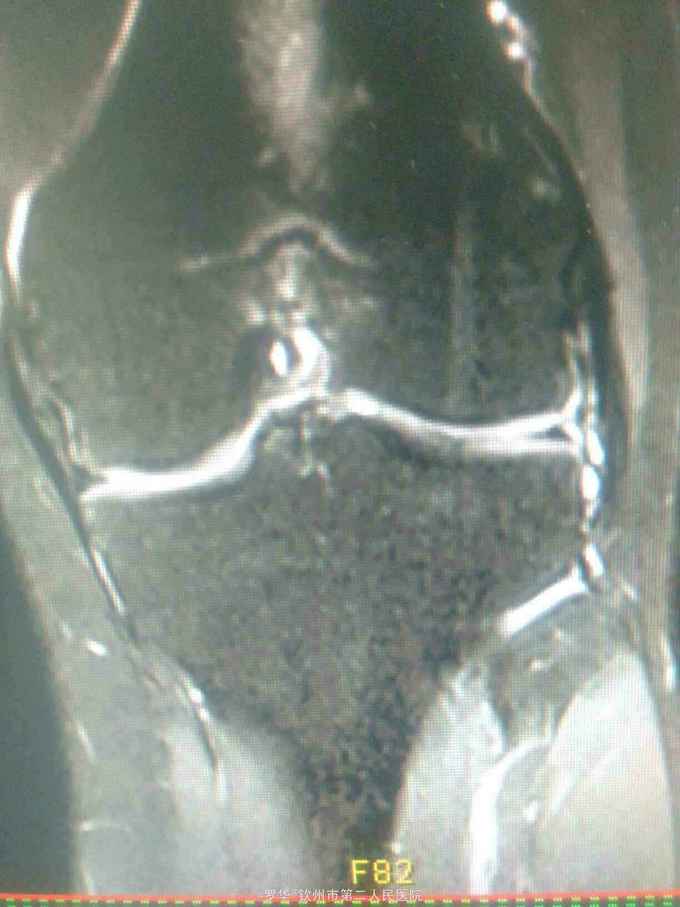

主诉:扭伤致左膝关节活动受限3月余。病史:患者男性,31岁,于入院3月余前扭伤左膝关节,致左膝关节肿痛、活动受限,尚可站立行走,但不能剧烈运动及重体力劳动,曾行磁共振检查提示左膝前交叉韧带损伤,半月板损伤,现为进上一步治疗入院。

查体:左膝关节无明显压痛,前抽屉试验阳性,侧方应力试验、麦氏征、研磨试验均阴性,膝关节屈伸活动可,余查体未见特殊。 辅查:膝关节磁共振提示左前交叉韧带损伤,左膝关节半月板损伤。

诊断:左膝关节前交叉韧带断裂,左膝关节半月板损伤。 治疗:予硬外麻下行左膝关节前交叉韧带重建术。